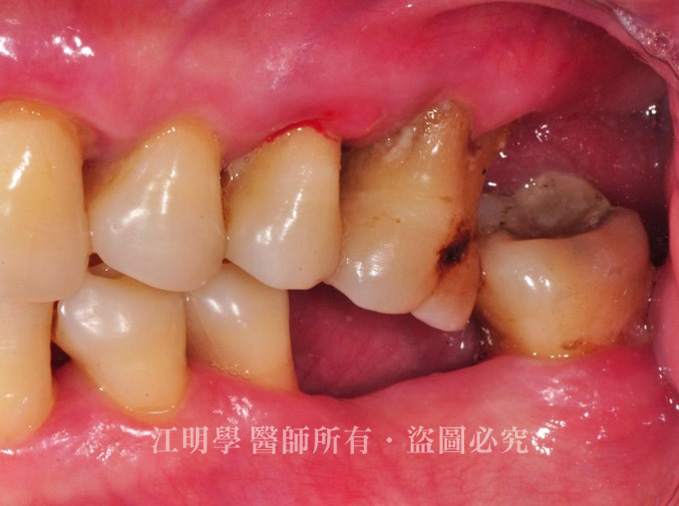

治療前

治療前:後牙多處缺牙導致咀嚼困難

後牙有多處缺牙,飲食上只能吃軟食,大笑時又會看到缺牙區,因為害怕看牙醫,拖延治療導致多處缺牙、牙周病問題嚴重。

1.先做根管治療,並拔除牙疾嚴重無法重建的殘根以降低感染風險。